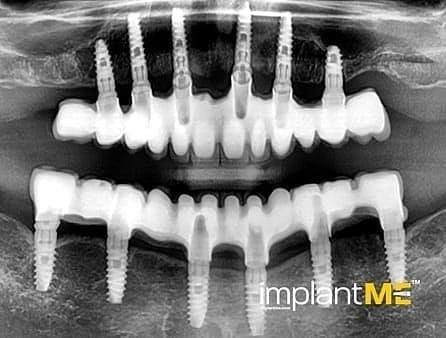

Атрактивните и особено здравите заби не се само одлучувачки дел од нашиот изглед, туку и на нашата личност. Во минатото, губењето на еден или повеќе заби имаше одлучувачка улога врз изгледот на луѓето. Поради модерната орална имплантологија, ова повеќе не е случај. Со релативно мали процедури за орална хирургија, индивидуалните или сите непостоечки заби можат да бидат заменети со импланти, естетски и функционално еднакви на природните заби. Преку вметнување импланти во форма на корен, можно е да се избегнат промени на соседните заби и да се зацврстат коронки што тешко може да се разликуваат од вистински заби во празнините на забите. Коронките или мостовите поддржани од импланти се прицврстени на колец зацврстен во коска, што им дава на пациентите џвакање со чувство скоро нималку различно од нивните заби. Во случај на потполна беззабост, имплантите може да претставуваат сигурна потпора за мобилна протеза, како и за големи фиксни мостови.

Забната протетика поддржана од имплант тесно се доближува до природните заби. Коронките водат со нивниот природен изглед, имплантите со нивната стабилност, а двете заедно со нивното позитивно влијание врз функционалното зачувување на целиот мастикаторен апарат.